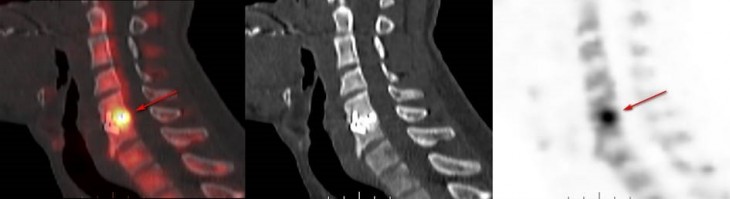

Lors du récent congrès de la Société Française de Chirurgie Rachidienne (SFCR) qui s’est tenu à Montpellier du 13 au 15 juin 2024, le Dr Jean-Edouard Loret, neurochirurgien, a défendu l’intérêt du TEP scan au 18F-FNa dans le diagnostic de la pseudarthrose après arthrodèse cervicale.

Ce travail a pu être réalisé grâce à l’étroite collaboration entre la Médecine Nucléaire Tourangelle et les services de Neurochirurgie situés sur les cliniques NCT+ et Léonard de Vinci.